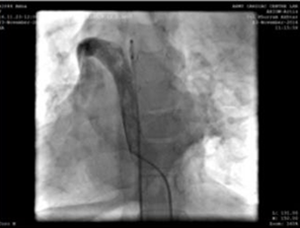

Nakłucie lewej żyły szyjnej i cewnik do angiografii 5F, pokazujący ścieżkę połączenia żyły górnej ramienia-żyły głównej górnej-prawego przedsionka.

Użyliśmy osłonki doprowadzającej 9F, która została przesunięta i umieszczona w opadającej aorcie nad super sztywnym prowadnikiem. MemoPartTM cone shape PDA occluder 14/12 mm, was attached to the delivery cable and progressed across the delivery sheath. The placement of the occlude was proper with no residual flow.